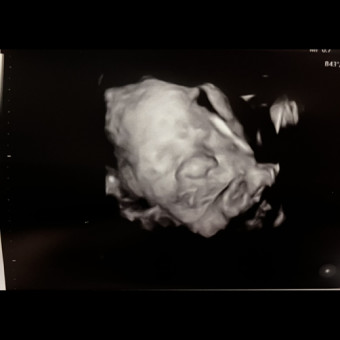

Hello everyone! Thank you for viewing our registry! ☺️ We are ready to welcome Madeline Jones Brewer in March 2026! 🩷

Pearhead "Love at First Sight" Sonogram Frame

babylist Icon

$12.99

target Icon

amazon Icon

from $9.99

I purchased this